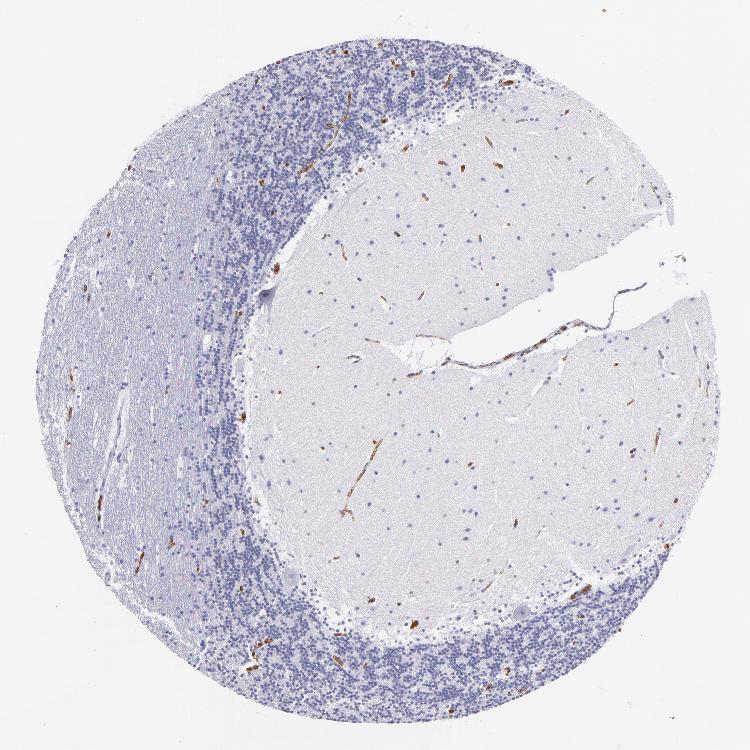

BRAIN CEREBELLUM Show tissue menu

CEREBELLUM - Expression summary

CEREBELLUM - Antibody stainingi

Antibody staining in the annotated cell types in the current human tissue is reported as not detected, low, medium, or high, based on conventional immunohistochemistry profiling in selected tissues. This score is based on the combination of the staining intensity and fraction of stained cells.

Each image is clickable and will lead to virtual microscopy that enables deeper exploration of all samples and also displays staining intensity scores, fraction scores and subcellular localization as well as patient and tissue information for each sample.

Antibody HPA014811Antibody CAB002658

Purkinje cells Not detectedNot detected

Cells in granular layer Not detectedNot detected

Cells in molecular layer Not detectedNot detected